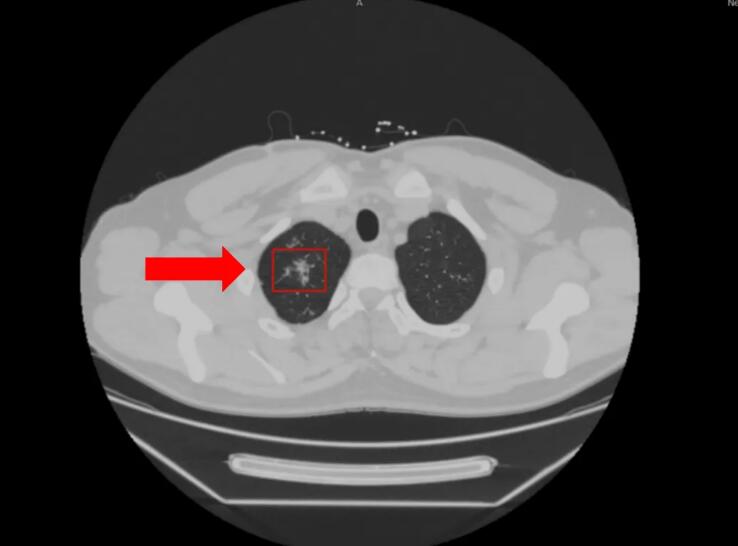

什么是电子气管镜下肺泡灌洗液 电子气管镜是一种通过电子技术成像的纤维支气管镜设备,具有高清晰的视觉效果,能够直接观察气管和支气管内的病变情况。在结核病的检查中,医生利用气管镜将生理盐水注入到患者肺部病变区域,轻轻灌洗并吸出一部分液体,这就是肺泡灌洗液。肺泡灌洗液包含了肺泡中潜在的细菌、炎性细胞及其他分泌物,能够反映肺部深处的感染情况,非常适合用于检测深部的结核菌。 Xpert MTB/RIF检测的优势 Xpert MTB/RIF检测相比传统的结核病检测方法(如痰涂片、痰培养)有以下明显优势: 检测速度快:传统的细菌培养需数周时间,而Xpert MTB/RIF仅需2小时即可出结果,大大缩短了确诊时间。 敏感性更高:与痰涂片及痰培养相比,Xpert MTB/RIF对结核菌的检测灵敏度更高,肺结核检测的准确率达94%以上,特别是对菌量较少的样本效果显著,而传统的检查阳性率只有30%左右。 耐药性检测:该检测能够同时检测利福平(结核病一线治疗药物之一)耐药性,为医生判断是否需调整抗结核治疗方案提供参考。 精准人群:该检测对于痰液样本难以获得的患者如咳痰困难的患者,或未形成痰液的早期患者群体尤为重要。 案例情况 一名年轻的男性患者,因“右侧胸背部疼痛3个月”就诊于我院呼吸与危重症医学科,胸部CT检查提示右肺上叶散在斑点、条索、钙化灶,慢性炎性病变可能。 根据胸部CT结果,初步考虑该患者为肺结核的可能。科室进行了电子气管镜肺泡灌洗,完善了肺泡灌洗液结核菌鉴定及耐药基因检测(Xpert MTB/RIF)等结核相关检查。 该患者Xpert MTB/RIF检测提示结核分支杆菌复合群阳性,结核病诊断成立。若根据传统的培养方法,不能寻找到该患者结核杆菌感染的有效证据,可能延误患者的诊断及有效治疗。 自该项技术开展以来,已经检测分析了两千余份样本,为临床诊断提供了可靠的依据,更加精准地检测肺结核,更好地控制结核病的传播,让更多患者得到及时治疗,实现更好的健康管理。